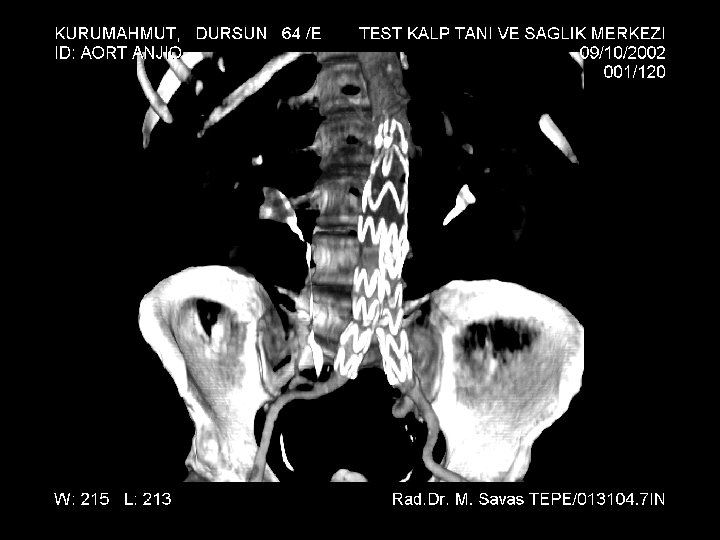

Infrarenal Abdominal Aort Anevrizması; Endogreft ile tedavi